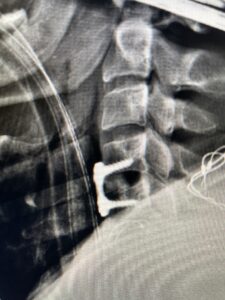

This 36-year-old female who had a long history of neck pain had a history on MRI of a C5-6 bulge. She recently after diving into a pool (not hitting her head on bottom) developed progressive problems with her arms. She had developed spontaneous shocks going down her arms and in the back of her neck. Spontaneous shocks going down the neck and spine is called a Lhermitte’s phenomenon and can occur with spinal cord compression and also with multiple sclerosis. On examination, the patient had long tract weakness of her arms, right greater than left. Her finger extensor weakness was profound on the right. MRI (Fig. 4) of the cervical spine revealed a massive C5-6-disc herniation causing significant cord compression right greater than left with subtle cord signal change. Because of the severe myelopathy, the patient was indicated for surgery. A C5-6 anterior cervical discectomy and fusion was performed (Fig. 5). The patient had a dramatic improvement of her strength in the recovery room.

Fig 5. Intraoperative Lateral Cervical X-Ray demonstrating C5-6 ACDF